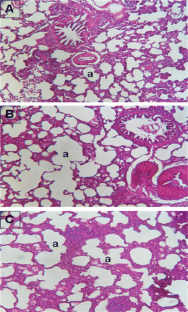

Fig. 3